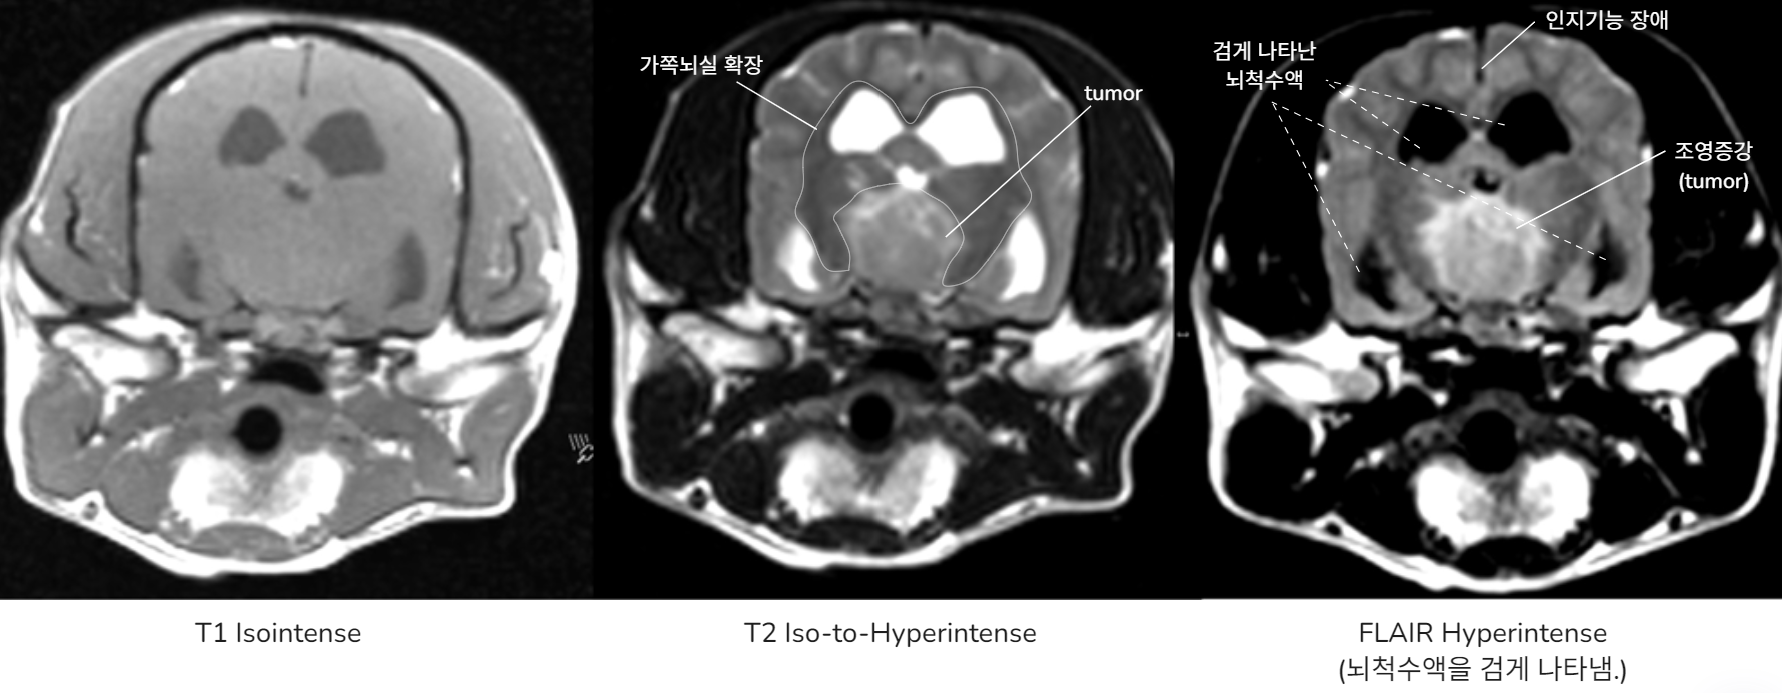

๐ Case 2. Congenital hydrocephalus - A

Hydrocephalus (์๋์ฆ)

- CSF ์ํ์ด ์ผ๋ถ ๋งํ์ ๋๋ ์ฒ์์ ์๋ฐ์ ์ค

- ์ฃผ๋ก ์ ์ฒ์ฑ, ์์ธก์ฑ์ผ๋ก ๋ฐ์.

| T1 | T2 |

|---|---|

![]() | ![]() |

- ์์ชฝ ๋ผ๊ฐ ๋น์ด ์์ (๊ตฌ๋ฉ, ์ฒ๊ณต)

- ๋์ฒ์์ก์ด ์ ๋น ์ ธ๋๊ฐ์ง ๋ชปํด ์ธก๋์ค์ด ์์ชฝ ๋ชจ๋ ํ์ฅ๋จ.

- ๋์ฒ์์ก์ด cerebral cortex๋ฅผ ๋๋ฅด๋ฉด์ ์์์ง.

โ ICP ๋์์ด ์์น, seizure ๋ฐ์

โ Severe Symmetrically ventriculomegaly (์ฆ, Hydrocephalus)

DAMNIT-V ์ค A์ ํด๋น. ์์น ์ ๋จ.